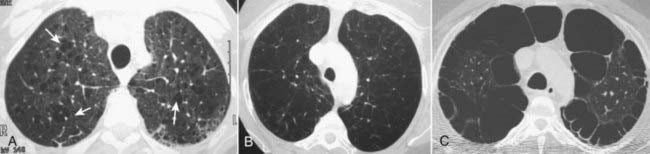

Figure 12-22 Types of emphysema.

A, Centriacinar (centrilobular) emphysema features focal destruction limited to the respiratory bronchioles and the central portions of the acinus (solid white arrows). It is associated with cigarette smoking and is most severe in the upper lobes. B, Panacinar (panlobular) emphysema involves the entire alveolus distal to the terminal bronchiole, is most severe in the lower lung zones, and generally develops in patients with homozygous alpha1-antitrypsin deficiency. C, Paraseptal emphysema is the least common form, involves distal airway structures, alveolar ducts, and sacs, tends to be subpleural, and may cause pneumothorax.

image Emphysema has three pathologic patterns:

Centriacinar (centrilobular) emphysema features focal destruction limited to the respiratory bronchioles and the central portions of acinus. It is associated with cigarette smoking and is most severe in the upper lobes (Fig. 12-22A).

Panacinar emphysema involves the entire alveolus distal to the terminal bronchiole. It is most severe in the lower lung zones and generally develops in patients with homozygous alpha 1-antitrypsin deficiency (Fig. 12-22B).

Paraseptal emphysema is the least common form. It involves distal airway structures, alveolar ducts, and sacs. Localized to fibrous septa or to the pleura, it can lead to formation of bullae, which may cause pneumothorax. It is not associated with airflow obstruction (Fig. 12-22C).